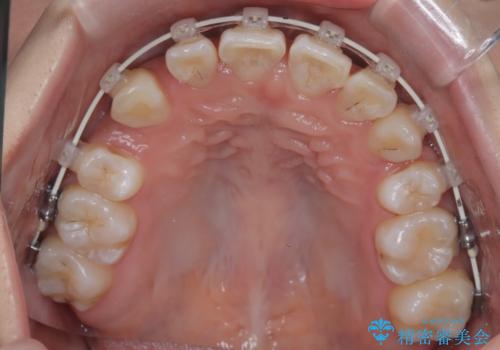

- 八重歯(叢生)と、上下の歯の中心線(正中)がずれていることを主訴にご来院されました。精密な検査の結果、歯列全体のスペースが大幅に不足しており、八重歯を正しい位置に配列し、正中のズレを改善するためには、上下左右の第一小臼歯を抜歯する必要があると診断。装置には、目立ちにくい審美ワイヤーを使用し、見た目を気にせず、機能性と審美性が完璧に整った咬み合わせを目指す治療計画を立案しました。

今回の矯正治療では、まず計画通り上下左右の小臼歯4本を抜歯し、八重歯や正中のズレを解消するための十分なスペースを確保しました。装置には、目立ちにくい白いブラケットとワイヤーを使用した審美ワイヤー矯正を採用。

八重歯: 突出していた八重歯を歯列内に誘導し、デコボコを解消しました。